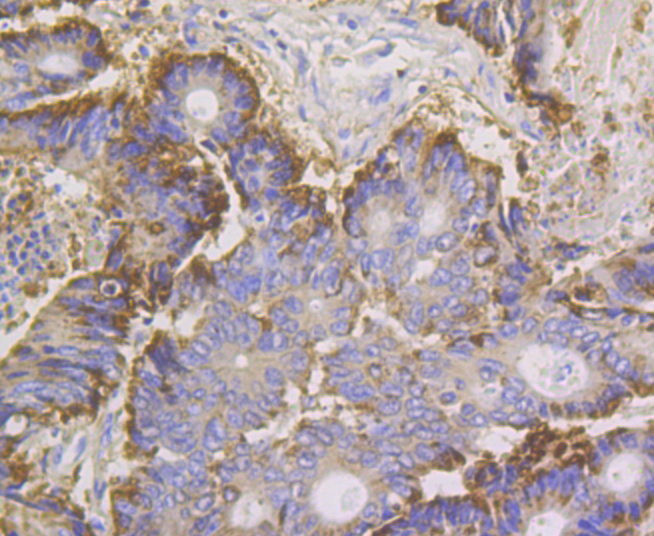

Annexin IV (1G2) Monoclonal Antibody

• IHC-P

Catalog # bsm-54390R

Product Name Annexin IV (1G2) Monoclonal Antibody

IHC-P 1:200-400